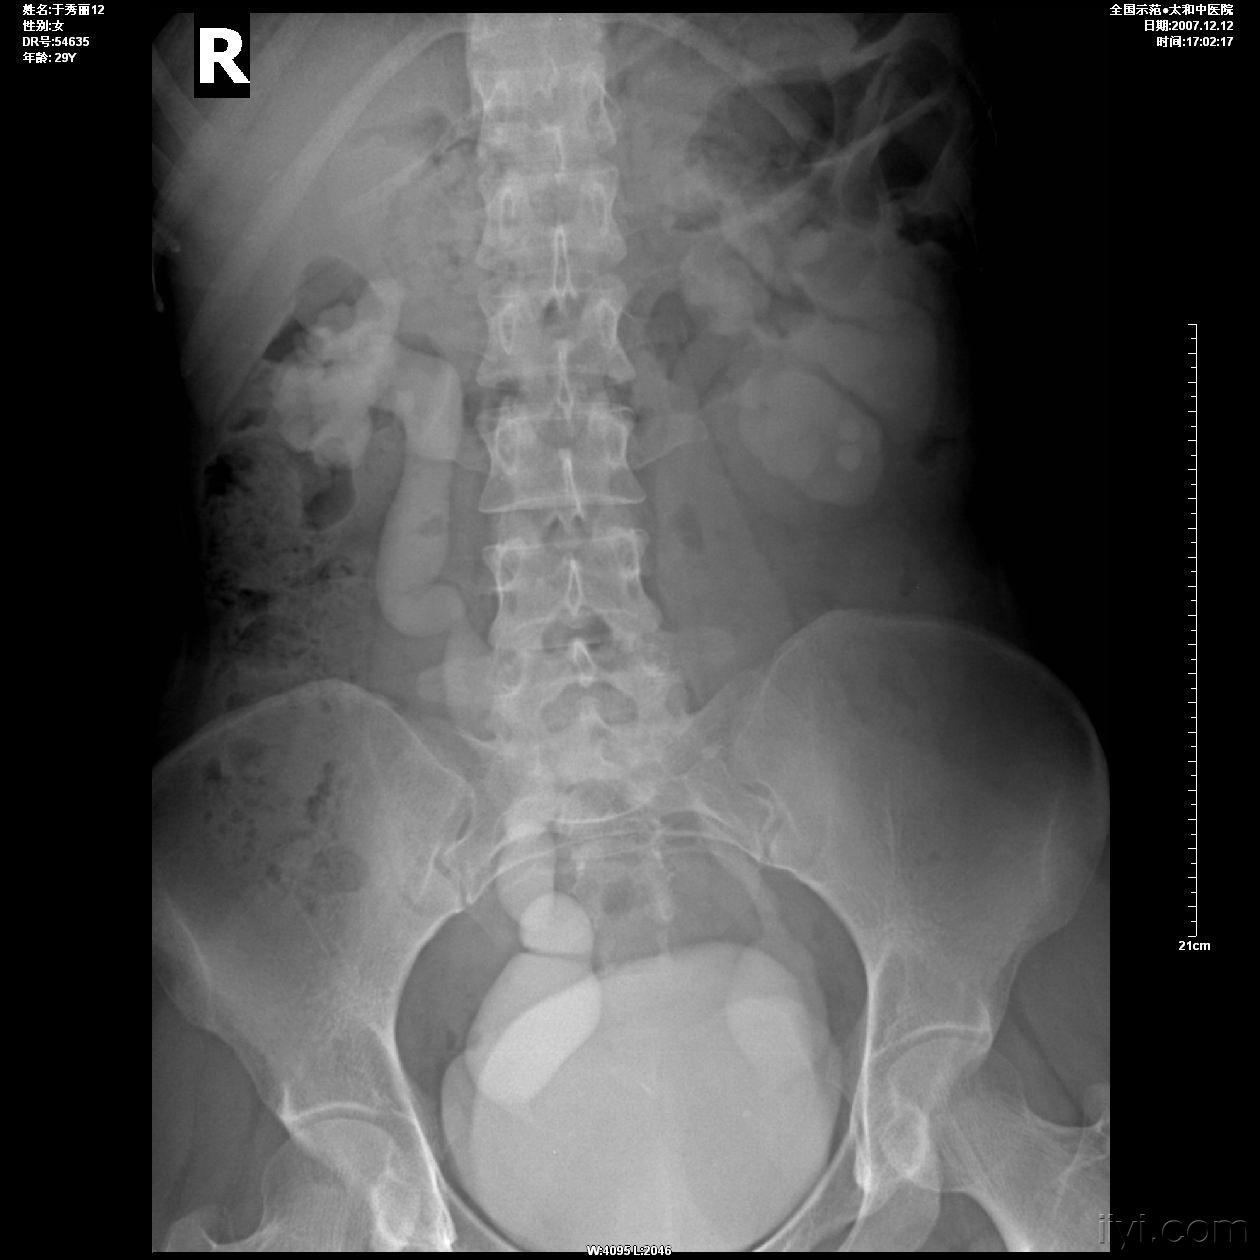

输尿管结石平片

143号作品:输尿管结石一例病例讨论

左侧输尿管末段巨大结石双侧输尿管结石输尿管镜碎石术后,复查腹平片

平片:左输尿管中段结石?左肾结石?有ivp结果

术前尿路平片